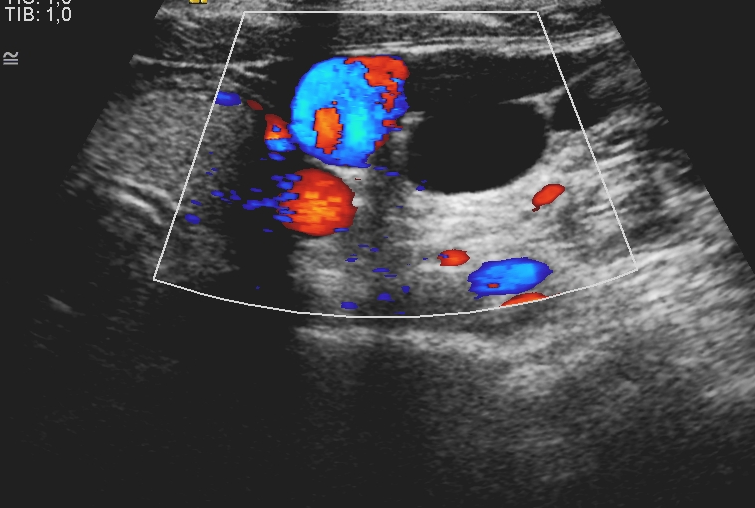

US – an ideal tool for the examination of neck soft tissue - can be first-line modality in case of palpable neck mass, thyroid enlargement, dysphagia and persistent hoarseness. US is widely available and capable of multiplanar, real-time visualization. US can determine whether a mass is cystic or solid and therefore able to differentiate between adenitis, cellulitis and abscess. One of the most frequent cystic neck mass is the branchial cleft cyst , which arises on the lateral part of the neck from a failure of obliteration of the second branchial cleft in embryonic development. Most common palpable neck mass in adults is related to metastatic lymphadenopathy, which is the early sign of pharyngeal or laryngeal carcinoma in many cases. A round, enlarged (> 10 mm) lymph node with loss of internal structure suggests malignancy. Enlarged lymph nodes in children are caused by lymphadenitis most frequently; however, in this case the central hilus remains echogenic and the internal structure is normal.

4. image: Young male patient with a left supraclavicular lump. Upper panel: complex cystic mass with sepatations; normal flow in the neighbouring vessels. Lower panel: T2W, postcontrast T1W, fat-saturation T1W MRI suggest cystic lymphangioma (Asklepios Klinik Altona, Hamburg)